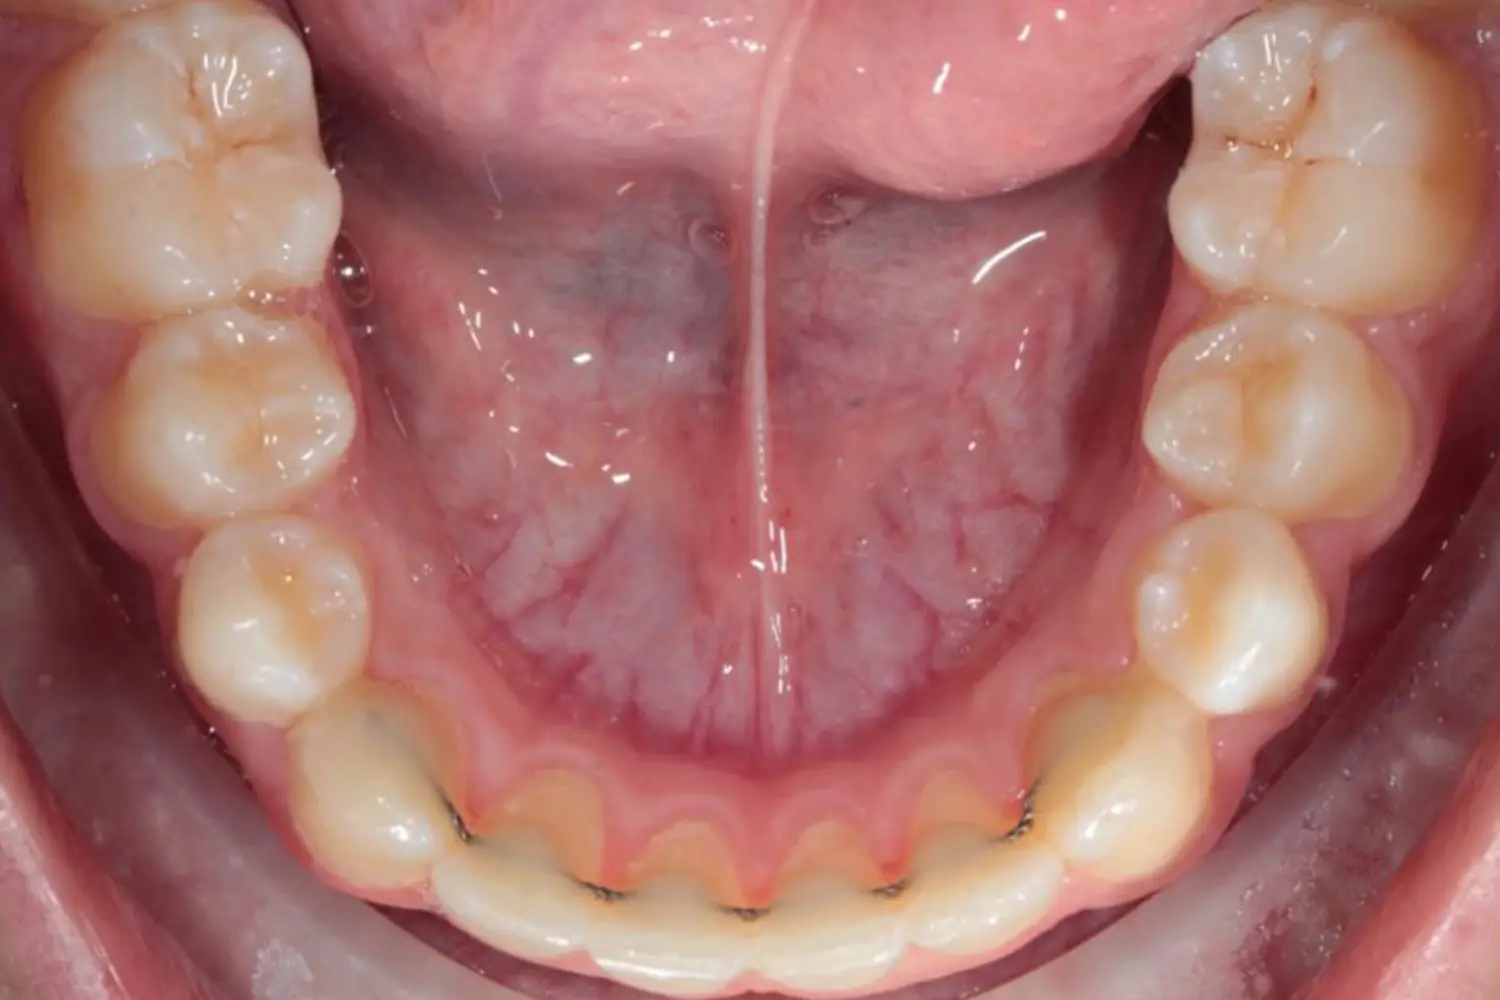

L’orthodontie linguale ou technique linguale consiste en l’utilisation de bagues, comme pour les traitements d’orthodontie plus « classiques », sauf que les bagues sont placées sur la face interne des dents pour que rien ne se voit à l’extérieur.

Comme pour les gouttières d’alignement, ce sont des traitements individualisés à chaque patient, faits sur mesure dans un laboratoire spécifique.

Ces traitements sont totalement invisibles et restent collés sur les dents, donc le patient n’a pas besoin de retirer son appareil lors des repas, contrairement aux gouttières d’alignement.

C’est un système qui passera totalement inaperçu auprès de votre entourage.

En effet, après le traitement d’orthodontie, qu’il ait été fait avec des bagues ou des aligneurs transparents, les dents doivent être stabilisées dans cette nouvelle position pour que le patient garde un sourire harmonieux à long terme. C’est pourquoi, après le traitement, un petit fil invisible est collé derrière les dents pour garantir la stabilité du résultat.